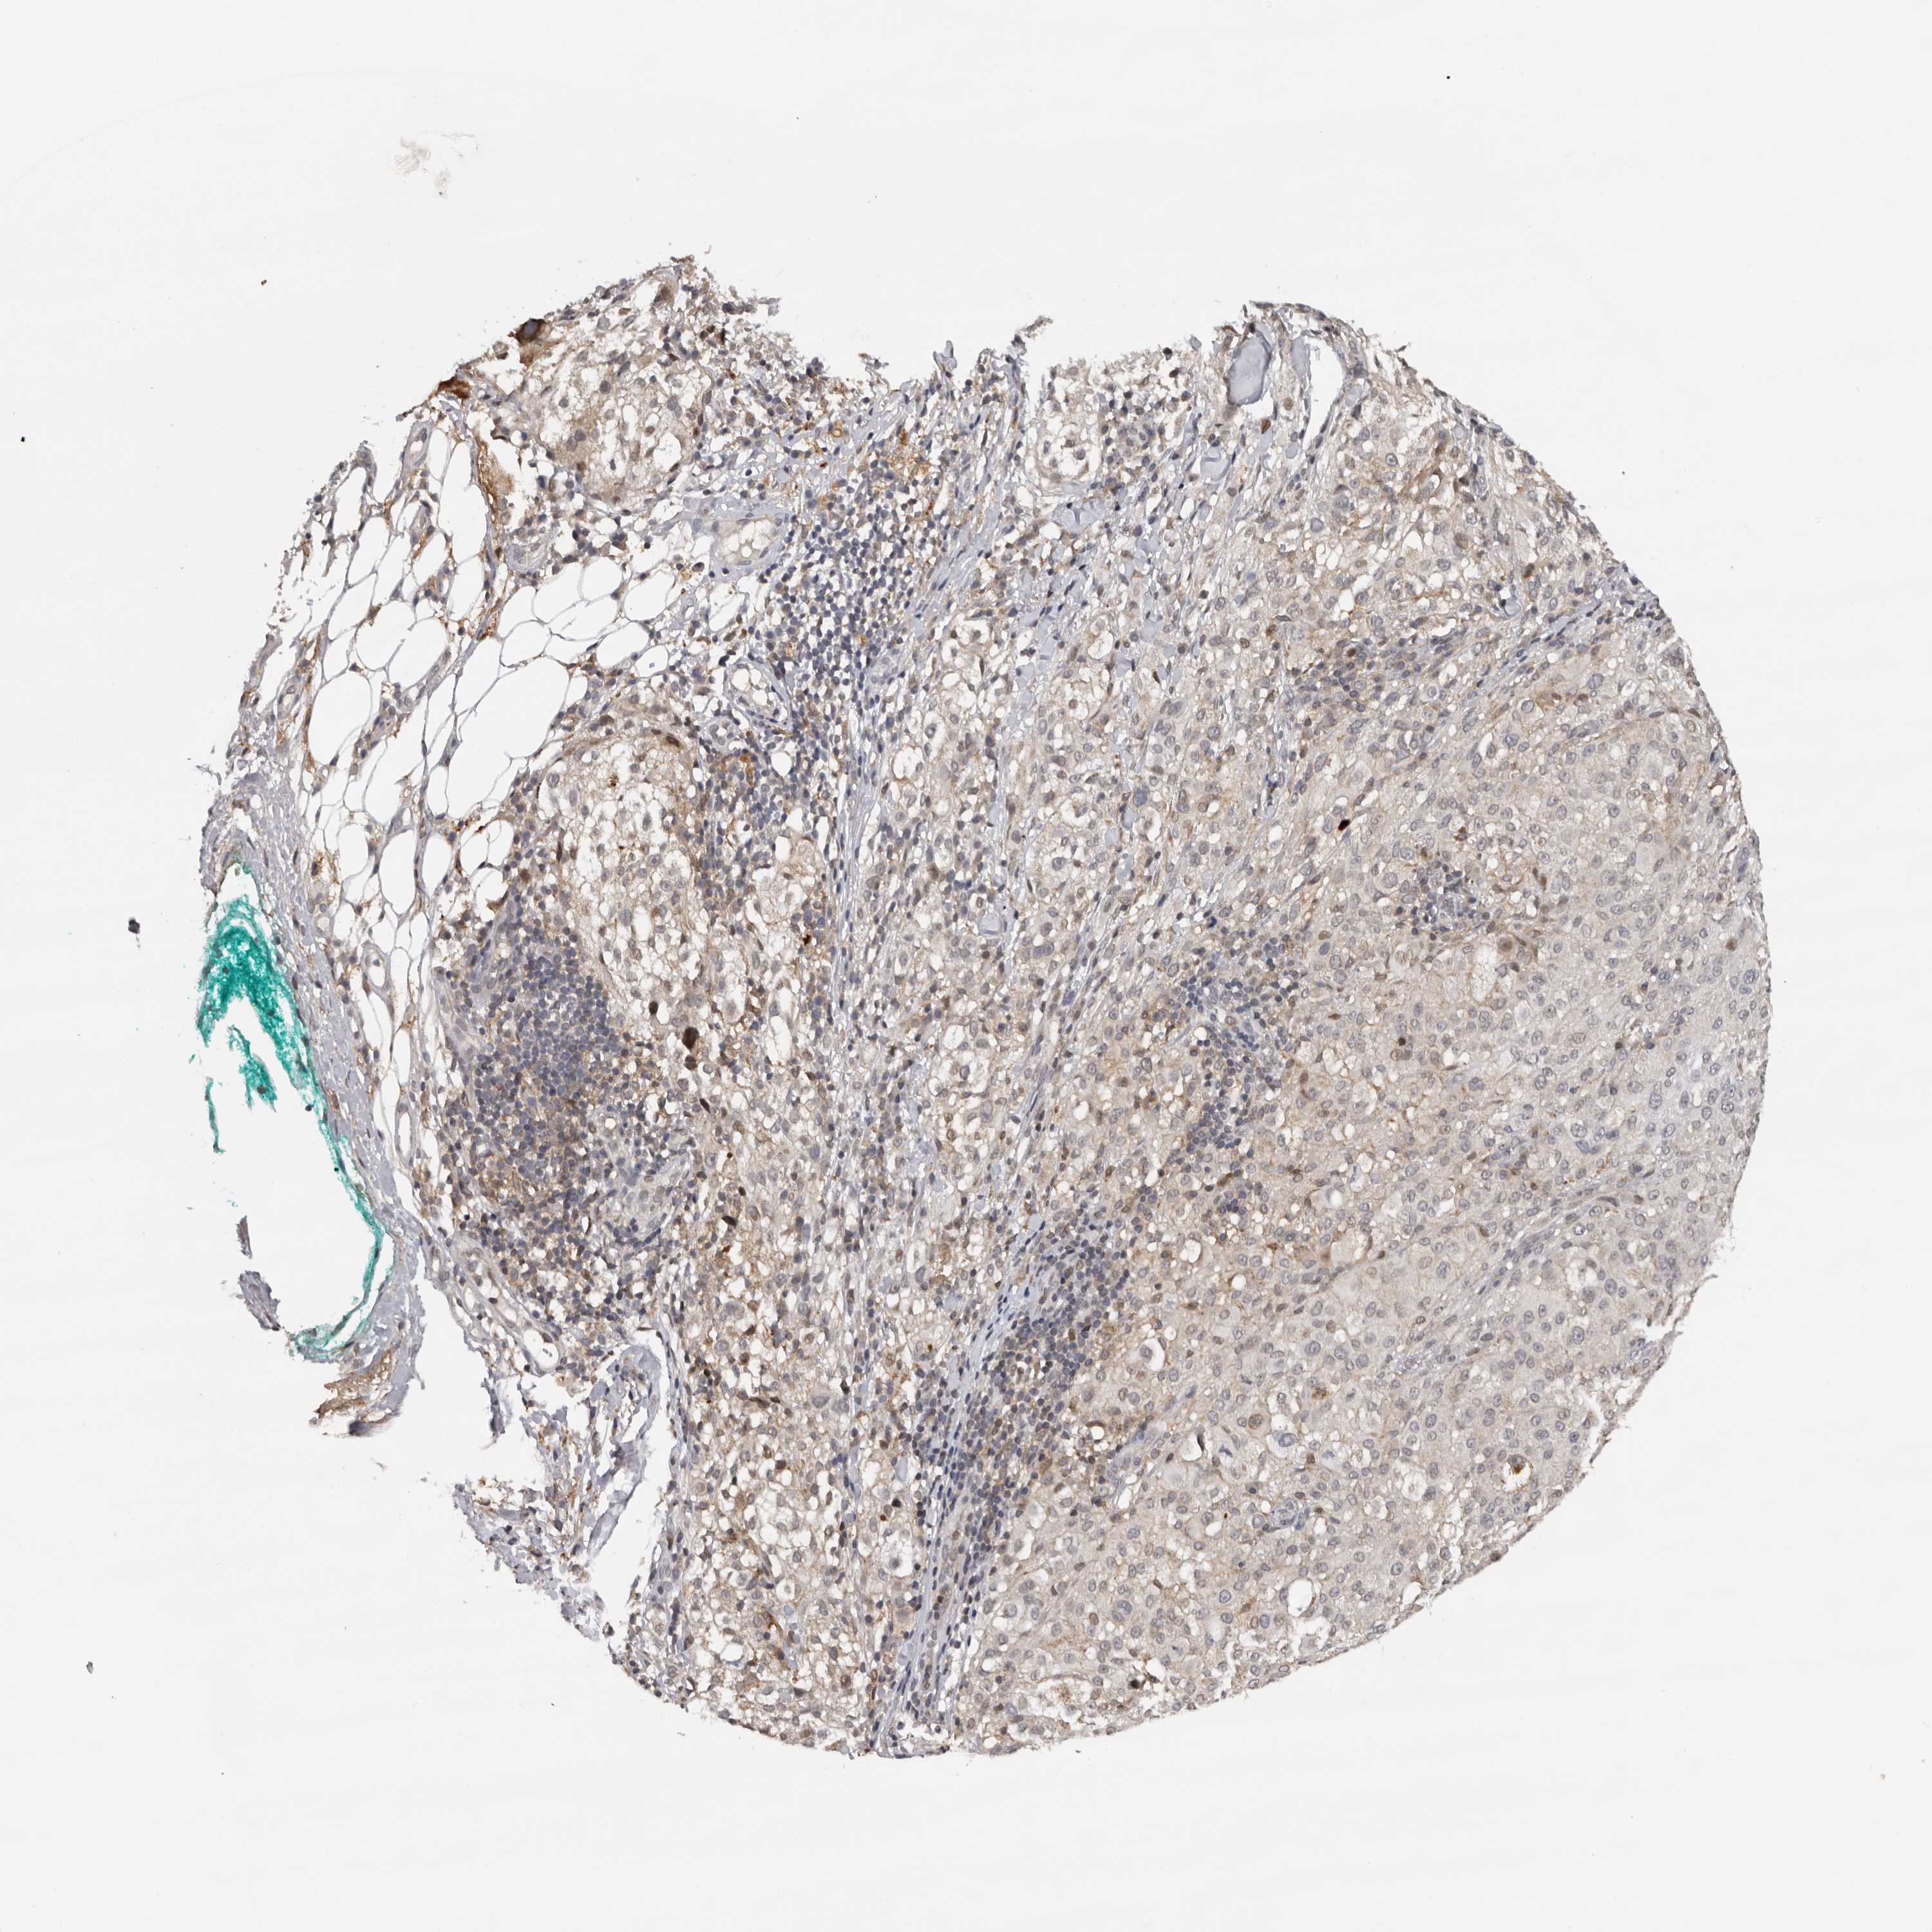

MELANOMA - Protein expressioni

A mouse-over function shows sample information and annotation data. Click on an image to view it in a full screen mode. Samples can be filtered based on level of antibody staining by selecting one or several of the following categories: high, medium, low and not detected. The assay and annotation is described here.

Note that samples used for immunohistochemistry by the Human Protein Atlas do not correspond to samples in the TCGA dataset.

Antibody stainingi

Antibody staining in the annotated cell types in the current human tissue is reported as not detected, low, medium, or high, based on conventional immunohistochemistry profiling in selected tissues. This score is based on the combination of the staining intensity and fraction of stained cells.

Each image is clickable and will lead to virtual microscopy that enables deeper exploration of all samples and also displays staining intensity scores, fraction scores and subcellular localization as well as patient and tissue information for each sample.

Antibody HPA023081

Antibody HPA023103

Antibody HPA024795

Staining

High

Medium

Low

Not detected

Intensity

Strong

Moderate

Weak

Negative

Quantity

>75%

75%-25%

<25%

None

Location

Nuclear

Cytoplasmic/membranous

Cytoplasmic/membranous,nuclear

Malignant melanoma, NOS

Malignant melanoma, Metastatic site